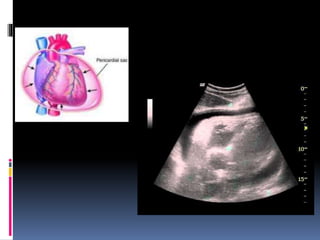

PERICARDITE

 FISIOPATOLOGIA: geralmente de natureza

inflamatória

 Superfície visceral do pericárdio não tem

inervação sensitiva.

 Dor resultante do comprometimento do folheto

parietal da pleura = pericárdio parietal tem

poucas fibras nervosas sensitivas aferentes, que

se dirigem ao SNC pelos nervos frênicos.

 Assim, a dor seria predominantemente

relacionada com a inflamação da pleura parietal

adjacente

 FISIOPATOLOGIA:

 Origem: Infecções (especialmente virais)

podem preceder o quadro; idiopática

 F.R.: trauma torácico, doenças autoimunes,

IAM, cirurgia cardíaca recente, uso de

procaínamida, hidralazina, isoniazida.

 Jovens

 Q.C.: dor retroesternal , tipo perfurante ou em peso,

que piora com inspiração profunda e tosse (tipo

pleurítica).

 Duração: horas a dias

 Pode irradiar para ombros, dorso ou pescoço

(irritação da pleura diafragmática)

 Se derrame pericárdico, dor pode aliviar na posição

sentada e inclinado para frente (patognomônico)

 Dispnéia (25-40%), febre (17%), atrito pericárdico

(até 85%)

 Como diferenciar atrito pericárdico de pleural na

ausculta? Som presente durante apnéia

 Se tamponamento cardíaco: estase jugular,

hepatomegalia, taquicardia, hipotensão e

pulso paradoxal ou sinal de Kussmaul

(consiste no aumento da turgência jugular, ou

das pulsações venosas durante a inspiração) .

 Tríade de Beck do tamponamento:estase

jugular, hipotensão, abafamento de bulhas